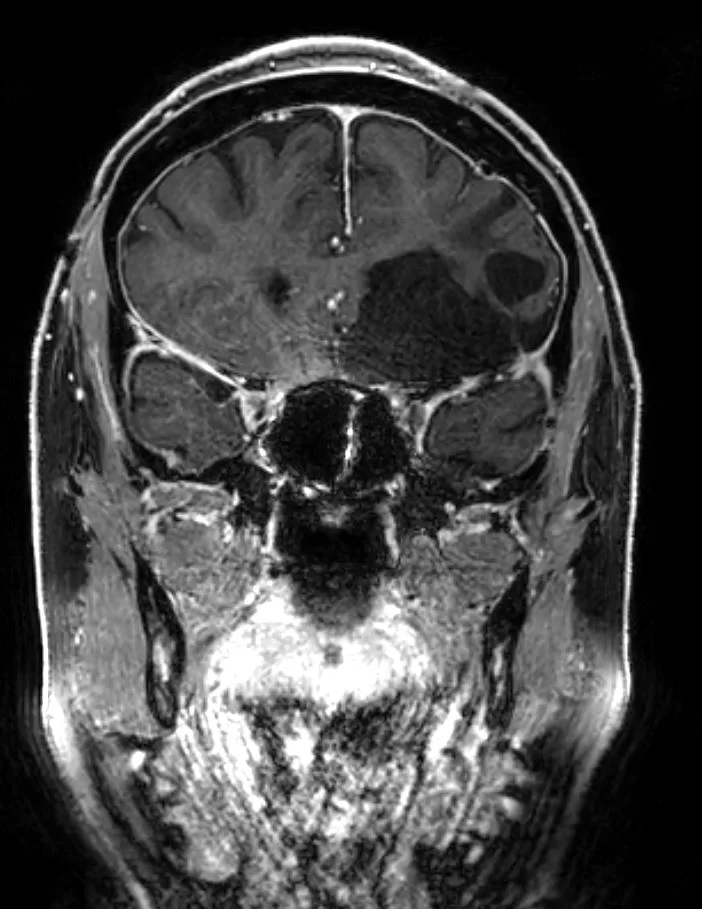

Η μετεγχειρητική μαγνητική τομογραφία εγκεφάλου δείχνει ολική εξαίρεση. Η ιστολογική εξέταση ανέδειξε μηνιγγίωμα (WHO I).

Μετεγχειρητικά η ασθενής ήταν σε άριστη νευρολογική κατάσταση και εξήλθε την 7η μετεγχειρητική ημέρα.